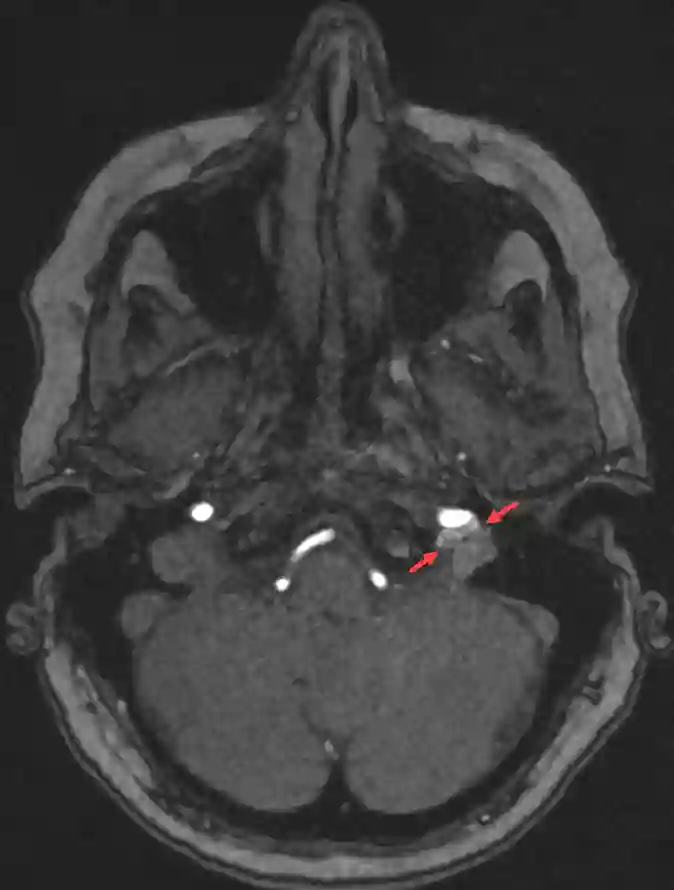

Paragangliom am linksseitigen Canalis caroticus in einer MRI TOF Sequenz.

Paragangliom im linksseitigen Canalis caroticus